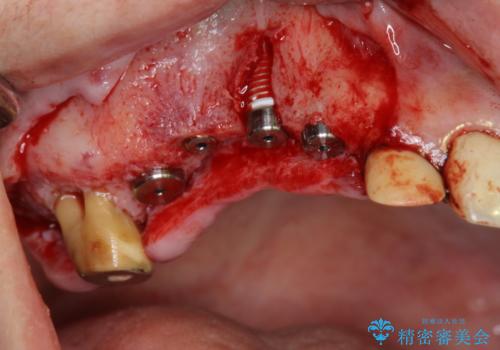

- 他院で1本インプラントを入れたまま治療に通うことができなくなり、途中からの治療を希望され来院されました。

既に埋入されているインプラントは位置が悪いのでそのまま骨内に留置することとし、新たに咬合機能を回復すべく3本のインプラントを埋入すると同時に吸収した骨幅を増やし、安定してインプラントで噛める環境整備を目指します。

インプラントが長持ちするために、インプラント周囲の十分な骨量・角化歯肉の存在・安定した咬合を一つづつ整備する治療を行いました。